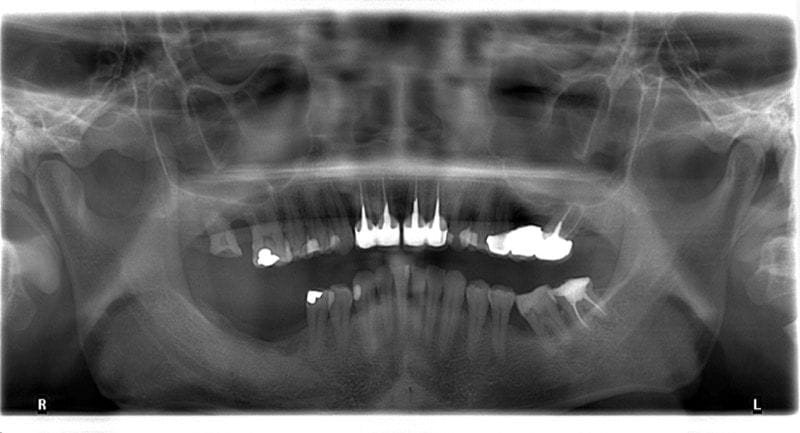

圖示:牙周病治療前,先以環口式X光片來完整檢查Mr.Lin的牙齒狀況

我們發現到患者的牙周與齒槽骨流失超過50%,缺牙一共有三顆。診斷是全口嚴重牙周病(第三期)。

圖示:被診斷為第三期全口嚴重牙周病的各角度口腔X光照

比照十年前的X光片,整體齒槽骨流失估計是10%,依照大部分牙周病的進展速度屬於中等(B級),但是在缺牙處旁的小臼齒區流失超過10%,破壞速度比較快(C級)。